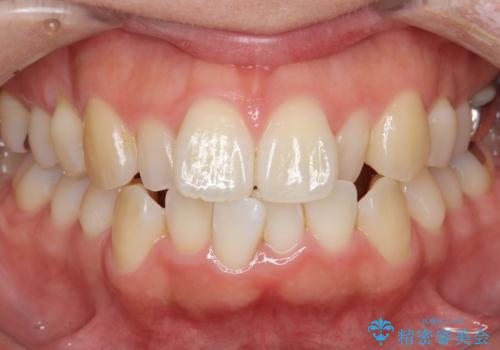

矮小歯 セラミッククラウンで綺麗に 30代女性

全顎的に歯並びにがたつきがあり、上の側切歯(上顎両側2)は生まれつき小さい歯(矮小歯)でした。

矯正治療後、矮小歯をセラミッククラウンにより理想的な歯の大きさに仕上げました。